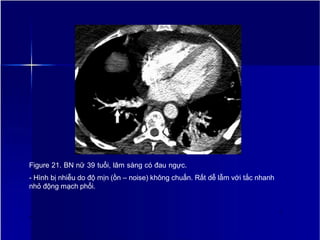

Figure 21. BN nữ 39 tuổi, lâm sàng có đau ngực.

- Hình bị nhiễu do độ mịn (ồn – noise) không chuẩn. Rất dễ lẫm với tắc nhanh

nhỏ động mạch phổi.